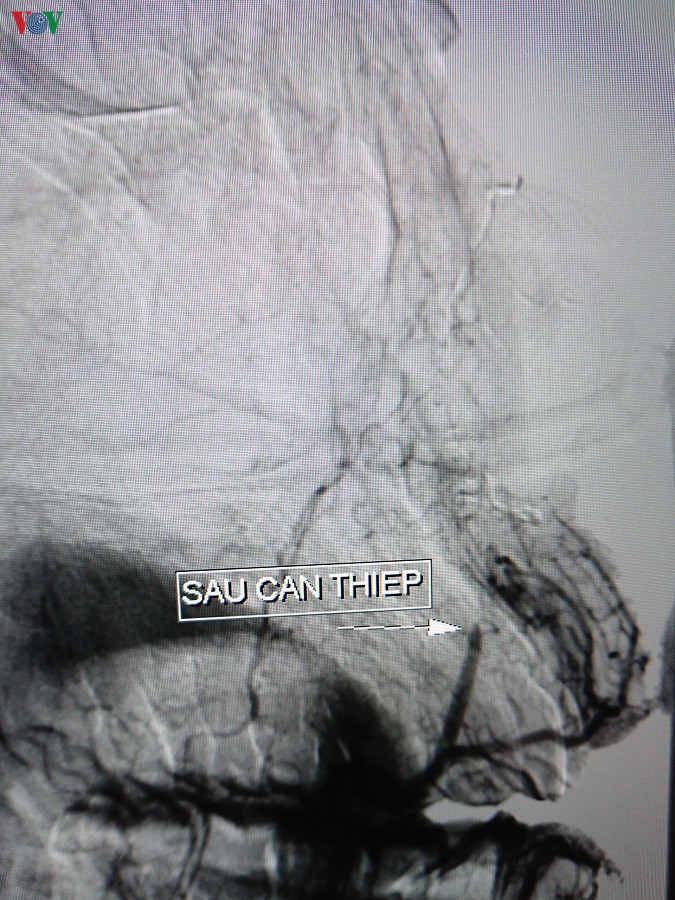

Hình ảnh sau can thiệp

Sau 3 giờ đồng hồ làm thủ thuật, tình trạng bệnh nhân ổn và không còn tình trạng chảy máu mũi. Hiện tại, bệnh nhân tỉnh táo, mũi ngưng chảy máu và sinh hoạt bình thường.